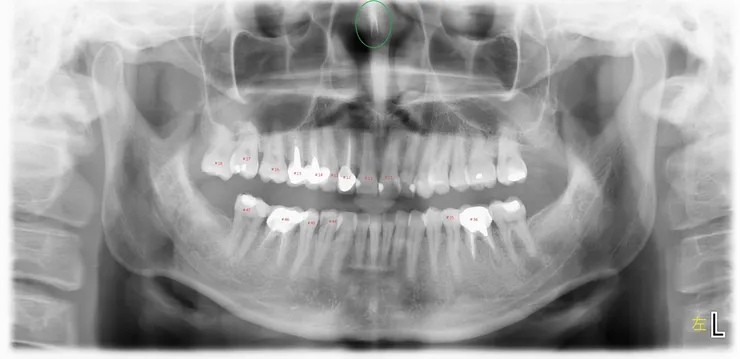

案例一